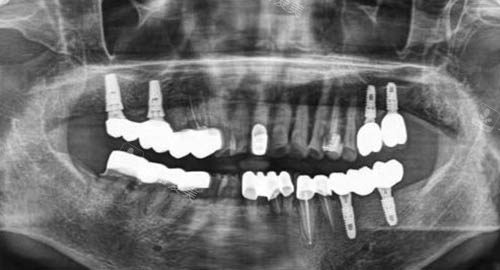

无论是常见的牙齿清洁、补牙,还是复杂的牙齿矫正、种植牙等项目,医生们都能够熟练操作,并且根据患者的具体情况制定个性化的治疗方案。

同时,清新口腔还不断引进新型的口腔诊疗技术和设备,如智能化口腔扫描仪、激光治疗设备等,为提高诊疗结果提供了有力的支持。